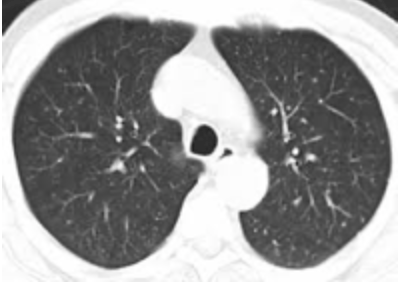

C. Chest CT-scanner

This test provides an imaging of the lungs to confirm the diagnosis of COVID-19, for example in case of negative RT-PCR despite a positive clinical picture (Clinical Score >/= 2).

Normal lung CT-scanner :

Abnormal lung CT-scan: Rx Thorax:

WARNING, these images are not specific to a COVID-19!

They are found in a group of pulmonary pathologies grouped under the generic term ARDS (Acute Respiratory Distress Syndrome) or SDRA (Syndrome de Détresse Respiratoire Acute).

So, as we can see, frosted glass lesions are typical of ARDS (or ARDS), not of any particular cause.

They are found in particular in infectious pneumonia with so-called atypical germs, such as Mycoplasma Pneumoniae, Chlamydia Pneumoniae or Legionella Pneumophila, but also in non-infectious pneumopathies.

A differential diagnosis must always be made, especially in people with one or more severe co-morbidities (diabetes, obesity, chronic kidney, lung or heart disease, etc.), which is the case for most people admitted to intensive care units during the COVID period.

The problem is to withhold a diagnosis of COVID without considering other possible causes, especially in the case of a negative RT-PCR.